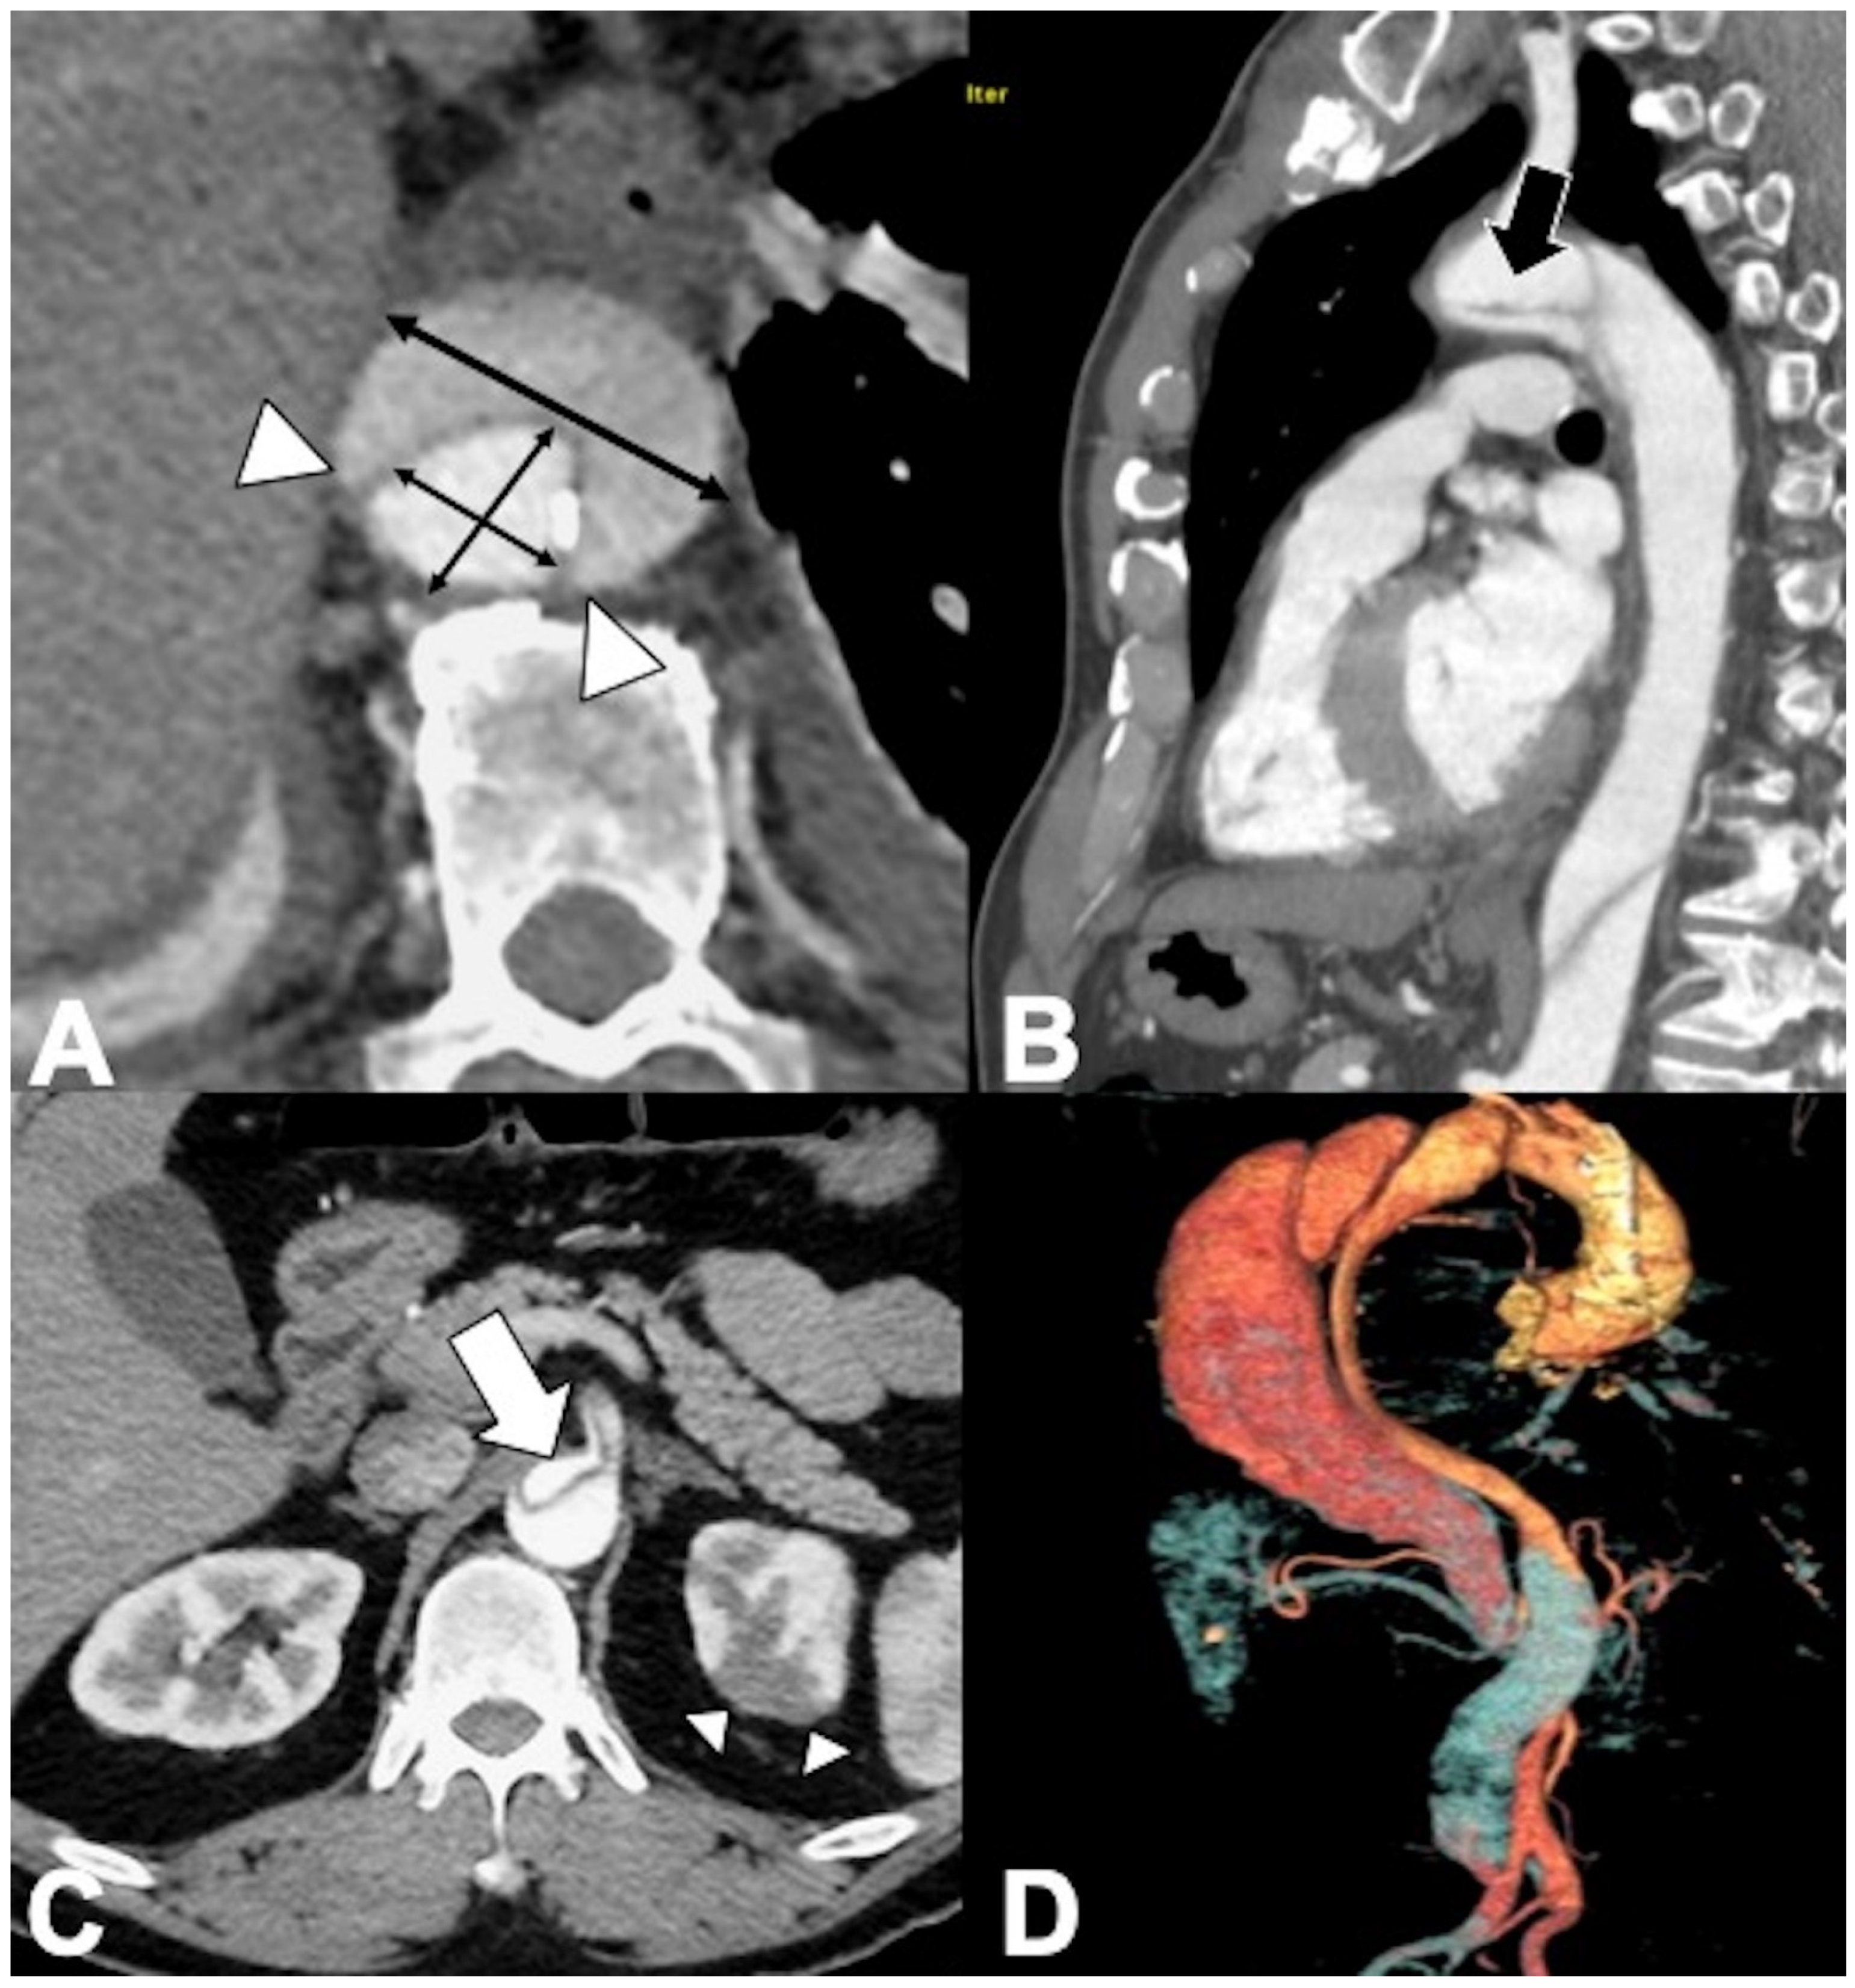

Malperfusion syndromes are less common in IMH patients than in AD, but periaortic hematoma and subsequent pericardial effusion are more common. After the initial detection and management of IMH, serial follow-up imaging is accomplished with CT or MRI to document resolution, stability, or progression. IMH conversion to dissection often occurs within 3–8 days (Figure 9). Development of an aneurysm (saccular or fusiform) is indicative of progressive weakening of all three layers of the aortic wall. The most frequent long-term complication of IMH is the development of aortic fusiform aneurysm secondary to structural weakness of the media, usually in the subacute or chronic stages of the disease [80,81,82]. A focal intimal disruption represented by contrast material-filled small pouch (<3 mm) projecting outside the opacified aortic lumen must always be sought on the baseline CTA; it can quickly become an ulcer-like projection (ULP) with a >3 mm communicating neck, which can progress to a frank double-barrel dissection. ULP is distinguished from PAU in that it typically is not present at the initial CT but is identified at follow-up imaging and may occur in patients with no evidence of atherosclerotic disease [84,85,86]. The appearance of ULP in the acute phase has a poor prognosis, particularly when it is in the ascending aorta or aortic arch, and frequently progresses to dissection, saccular pseudoaneurysm, or rupture. Intramural blood pool (IBP) or aortic branch artery pseudoaneurysm is a focal contrast pooling (hematoma) measuring at least 10 mm in thickness and arising along the nonpleural circumference of the aorta; communicating with and typically located at the origin of an aortic side branch (e.g., bronchial, intercostal, intercostobronchial, pericardial and lumbar artery), it has a very small (<2 mm) or imperceptible communication to the aortic lumen [21,24,25]. IBPs do not adversely affect prognosis, often regress spontaneously, and require no dedicated treatment [21,24,25,81].

Figure 9. Unstable Type A IMH complicated by ulcer-like projection (ULP). (A) Coronal oblique CTA shows type A IMH (arrowheads) in a 68-year-old man with hypertension and chest pain. The total aortic diameter was less than 50 mm and the IMH thickness less than 11 mm; he underwent medical management initially. (B) Three-day follow-up coronal oblique CTA image shows disease progression by an ULP due to opening of intimal tear (arrow). (C) 3D-volume-rendered (VR) reconstruction confirms ULP (arrow).